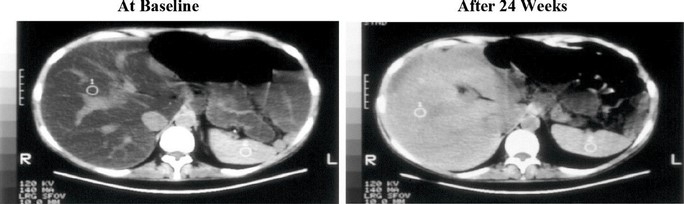

Figure 3. Liver CT Images: Before and After Treatment with IV Choline Chloride

Upon conversion of the quantification of computed tomography (CT) values to magnetic resonance imaging proton density fat fraction (MRI-PDFF), significant differences in the least square (LS) mean change from baseline in estimated MRI-PDFF were observed in the IV Choline Chloride group in comparison to placebo group at Week 4 through Week 24, demonstrating a clinically meaningful and statistically significant reduction in steatosis. When LS mean percent changes from baseline in MRI-PDFF were compared between treatment groups, significant differences in LS mean changes (range, 31.7% to 53.6%) were observed from Weeks 4 to 24 with p-values of 0.0009 to 0.0297 favoring the IV Choline Chloride group.

Steatosis: